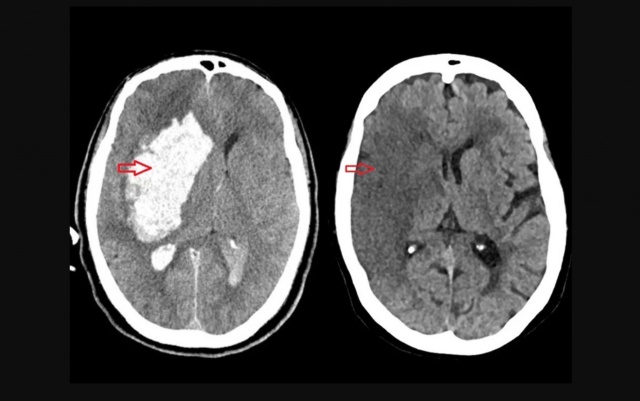

Foto: Neurolink.med

O AVC pode ser isquêmico (quando há entupimento de vasos sanguíneos, responsável por 85% dos casos) ou hemorrágico (causado por rompimento de vasos). O primeiro é mais comum; o segundo, mais grave.